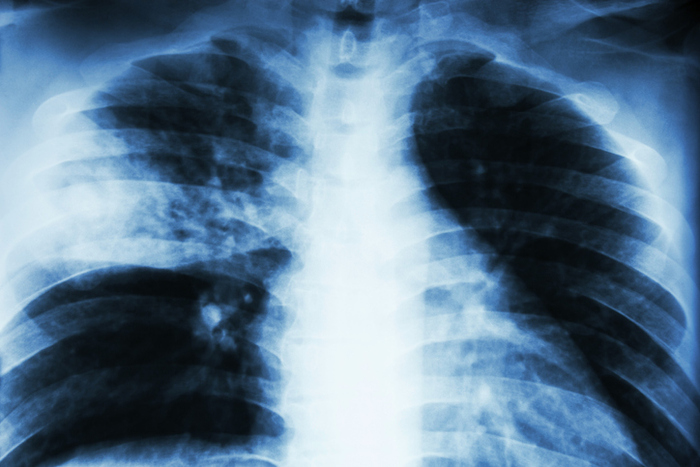

폐렴은 폐의 허파꽈리(폐포)에 염증이 생기는 질환입니다. 이 염증은 세균, 바이러스, 곰팡이 등 다양한 원인에 의해 발생할 수 있어요.

폐렴은 전 세계적으로 많은 사람들에게 영향을 미치는 질병으로, 특히 면역력이 약한 어린이나 노인에게 위험할 수 있습니다.

폐렴 증상은 사람마다 다르게 나타나지만, 일반적으로 기침이나 발열 같은 호흡기 증상이 주를 이룹니다.